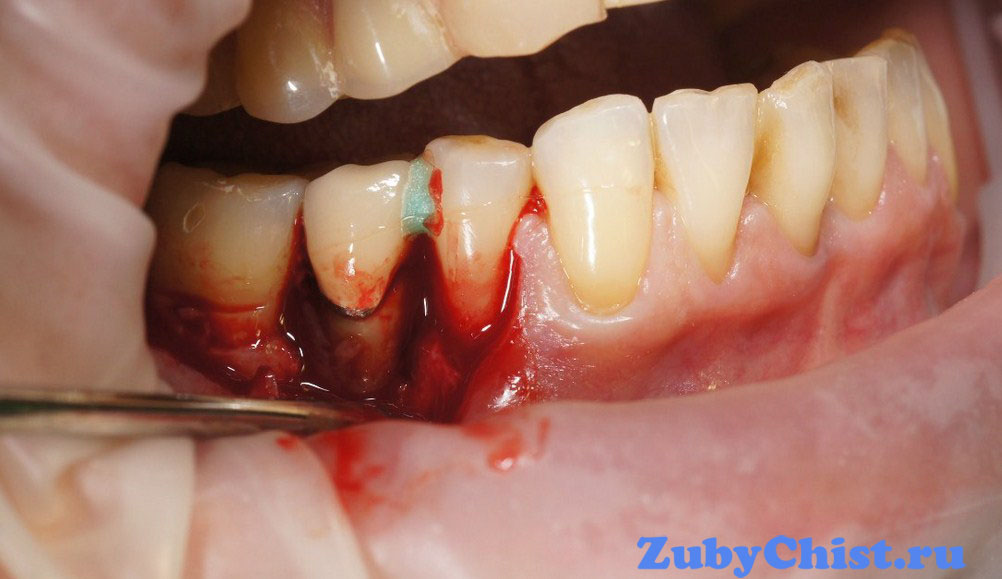

Когда на рентгеновском снимке выявлена серьезная атрофия костной ткани челюсти, а пациент жалуется на шатающиеся зубы и другие симптомы запущенного пародонтита, понадобится операционное вмешательство в виде кюретажа открытого типа. Используя стоматологический хирургический инструментарий, врач делает надрезы десны в области межзубных сосочков и отслаивает лоскуты мягких тканей. Таким образом он получает доступ ко всей внутренней поверхности зуба (шейке, корню) и может полностью вычистить пародонтальный карман от грануляционной ткани, остатков разрушенного цемента и вредоносных бактерий. После этого при необходимости на костный базис накладывается синтетический заменитель кости, которой стимулирует наращивание челюсти для укрепления зубов в лунках. Процедура занимает порядка двух часов для сегмента из 7-8 зубов, после этого десна зашивается. Снятие швов производят через 1-2 недели.

Кюретаж лунки зуба и сегментарная чистка корней при пародонтите проводится при помощи специальных инструментов: хирургической кюреты (отсюда и название операции) и ультразвукового скалера. Ими удаляются новообразования и налет, после чего при необходимости осуществляется подсадка синтетических костных тканей и зашивание монофиломентовой (желательно) нитью.